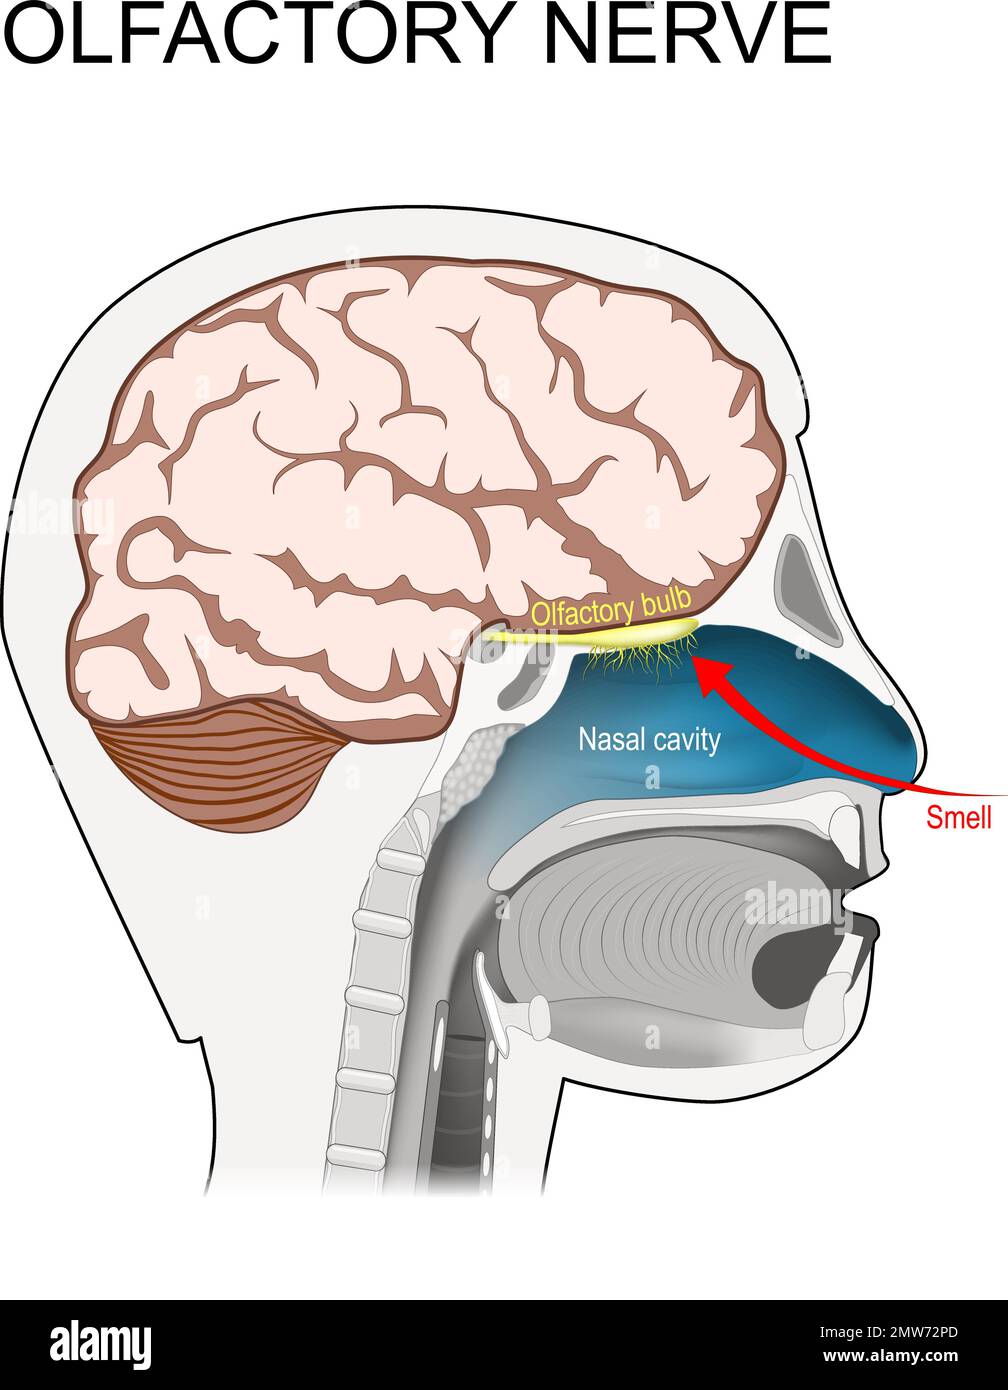

RF2MW72PD–nervo olfattivo. posizione del primo nervo cranico. Sezione trasversale di una testa umana con cervello, cavità nasale, bulbo olfattivo e recettori dell'odore

RF2J7343T–Tipi di neuroni: Cellule piramidali della corteccia cerebrale, cellule Purkinje della corteccia cerebrale, cellule olfattive dell'epitelio olfattivo